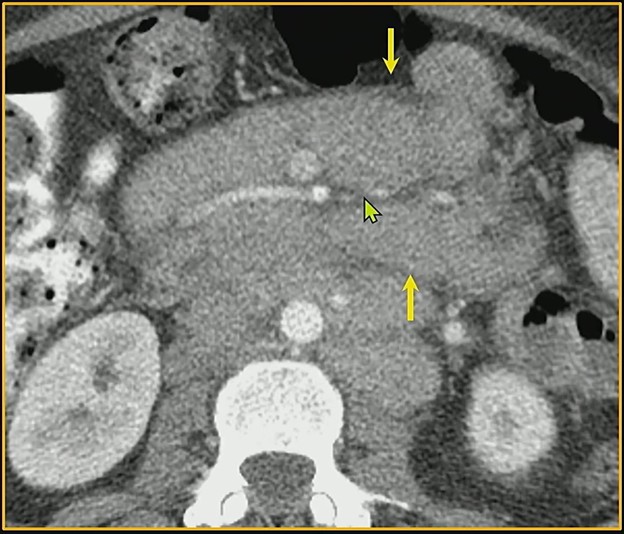

Bread & Butter Tip: The “sandwich sign“occurs when mesenteric masses involve both leaves of the mesentery while relatively preserving the central fat and vasculature. This creates a layered appearance, kinda resembling a sammy.

Bottom Line: Whereas lymphoma can share features with mesenteric panniculitis (e.g., relative mass effect, tumoral pseudocapsule delineation, the fat ring sign), the latter is dominated by fat necrosis and inflammation—rather than the bulky, “sandwiching” masses seen in malignant disease.